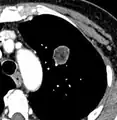

CT scan

For incidentally detected nodules on CT scan, Fleischner Society guidelines are given in table below. For multiple nodes, management is based on the most suspicious node.[8] These guidelines do not apply in lung cancer screening, in patients with immunosuppression, or in patients with known primary cancer.[8]